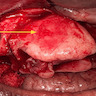

Clinical images

Gross description

- Well circumscribed tumor that can be shelled out easily in one piece